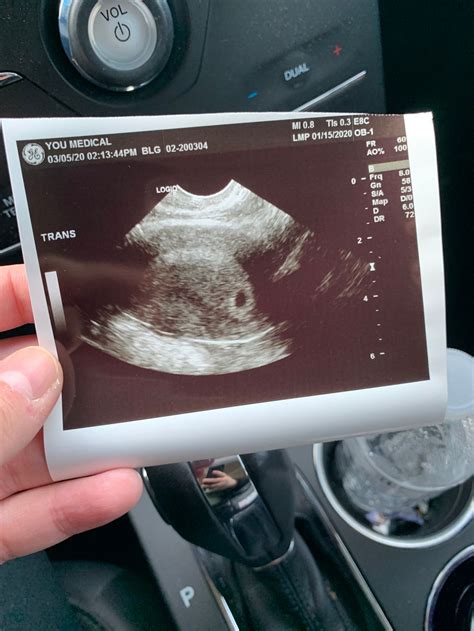

An Ultrasound at 4 Weeks is typically performed transvaginally, as it provides a clearer image of the uterus and the developing embryo at this early stage. The procedure is non-invasive and generally painless, although some women may experience slight discomfort. The ultrasound technician will use a wand-like device covered with a condom and lubricated with gel, which is inserted into the vagina to capture images of the uterus.

• Gestational Sac: This is the first structure visible on the ultrasound, appearing as a small, fluid-filled sac within the uterus.

• Yolk Sac: As the gestational sac develops, a yolk sac will form within it. This sac provides essential nutrients to the embryo before the placenta takes over.

• Embryo: At 4 weeks, the embryo itself is very small, often measuring less than 1 mm. It may not be visible on the ultrasound, but the presence of the gestational and yolk sacs is a positive sign.